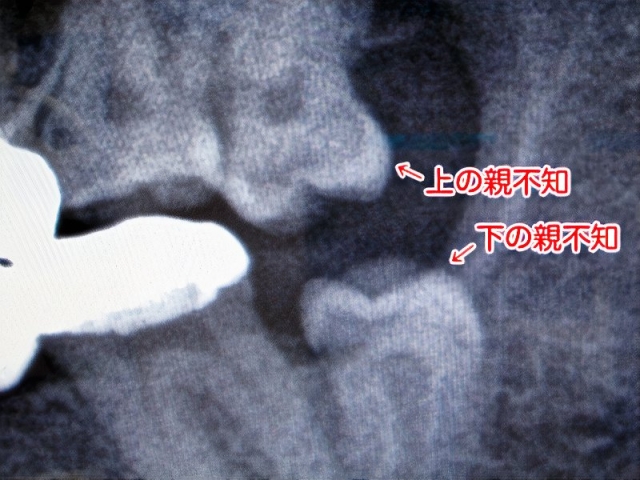

レントゲンの結果、意外な事が分かった。右下の親不知が痛んでいたのは、その上の親不知が原因だったのだ。上の親不知が下の親不知に当たって痛かったのである。上の親不知を抜けば今までの様な痛みは消えるという。

それよりも更に気がかりなのが左下の親不知である。今回のレントゲンで明らかになったのだが、嫌な角度で生えているのだ。これを抜くのはちょっと大変らしい。ああ、困った。

0036_photos_v2_x2.jpg

嫌な生え方をしている